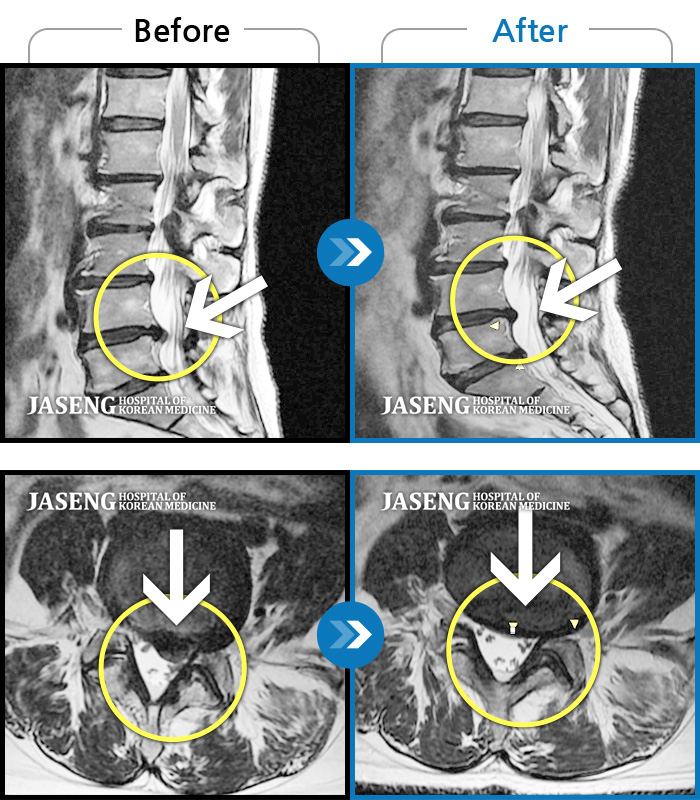

허리디스크

해운대 · 이상건 원장

허리통증 및 우측 하지 저림과 근력 저하

촬영시기

2018.02.05 ~ 2018.08.25